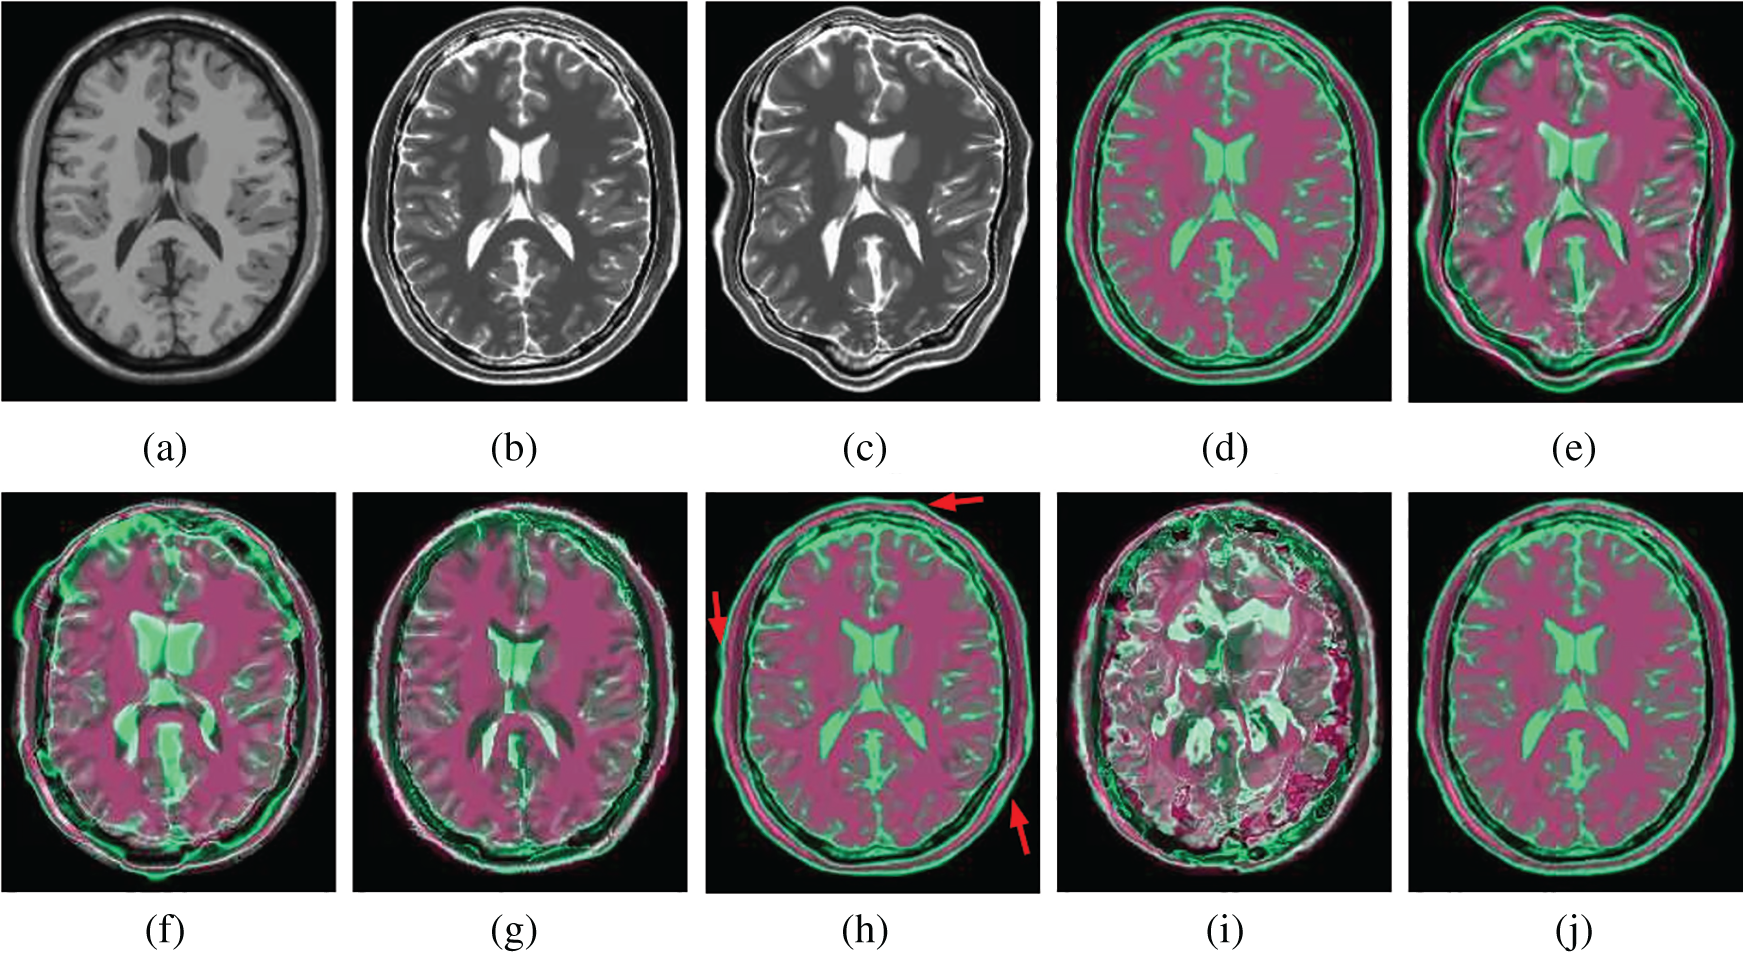

Figs. 7 and 8 show how well different registration algorithms perform in the application of registering a pair of images from the different image modalities. Fig. 7a is the fixed T1 MR image; Fig. 7b is the corresponding T2 MR slice (ground truth); Fig. 7c is the moving T2 MR image generated by distorting image (b) with

Figure 7: Illustration example of T1-T2 images from BrainWeb with different registration methods. (a) Fixed T1 (b) True T2 (c) Initial moving image (d) Ground truth overlay (e) Unregistered (f) Demons (g) SIFT Flow (h) Elastix (i) VoxelMorph (j) Siamese Flow

From the results in Tab. 3, Figs. 7, and 8, the proposed algorithm is shown to be capable of registering multimodal deformable images. Demons and VoxelMorph fail to align two images in the case of appearance variations across different modalities because they assume that illumination is constant between images. SIFT Flow also fails because the SIFT feature is based on the gradient information and does not consider multimodal information. Unlike Demons, SIFT Flow and VoxelMorph, Elastix and Siamese Flow perform well in these cross-modality registration tasks. In addition, from the MI results in Tab. 3 and the color coding results in Figs. 7 and 8, particularly the red arrows pointing in Fig. 7h, Siamese Flow is shown to perform better than Elastix, which uses handcrafted mutual information as a cost function to measure image similarity under a global statistical assumption. However, Siamese Flow calculates image similarity via metric learning image features, making it more suitable for deformable medical image registration and allowing it to produce more accurate results.